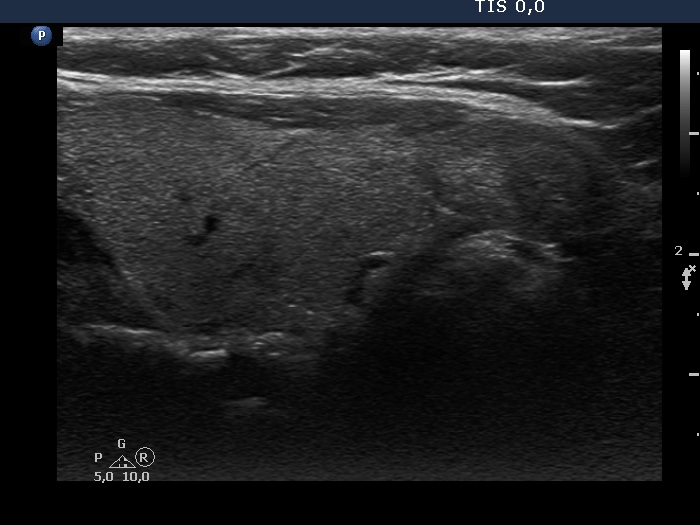

Ultrasonography. The thyroid was echonormal. There was a moderately hypoechoic nodule in the isthmus. The nodule had several intranodular hyperechogenic figures, probably back wall figures. The nodule did not show increase in size over the part two decades.